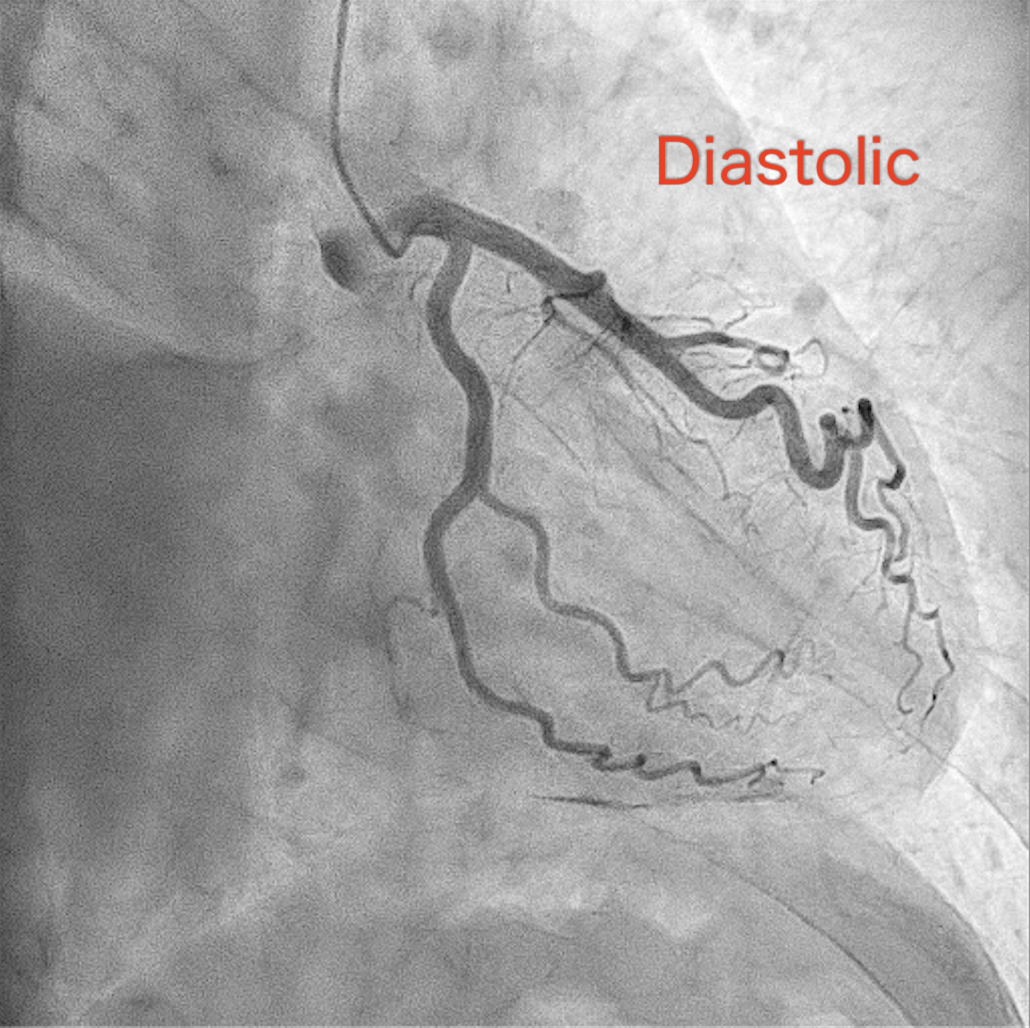

Coronary angiography revealed a distinctive finding in which the vessels and branches covering mid- to apical region of the left ventricle did not completely move in conjunction with the cardiac cycle, while those covering basal-part myocardium and running along left atrioventricular groove remain synchronized with the heart motion. This unusual finding was explained by the hard-and-fixed pericardium firmly adhered to the myocardium constraining the pulsation of the relevant part of the coronary tree. (Fig7-8) To obtain a more detailed anatomical and functional assessment, cardiac computed tomography (CT) was performed. The CT study further confirmed the absence of the usual counterclockwise rotational motion of the left ventricular apex during systole, a finding that was in complete agreement with the previously observed coronary angiographic pattern. In addition, the imaging revealed impaired diastolic filling of both ventricles, diffuse pericardial thickening, and signs of pericardial adherence, all consistent with the diagnosis of constrictive pericarditis.